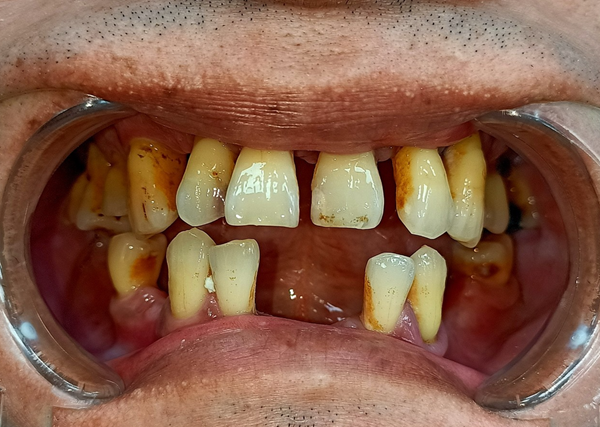

老實說,身為一個小上班族,看著 62 歲的爸爸每天看著想吃的東西不能吃而皺著眉,好像咬一口肉也能把人生咬到困擾深處,真的會心酸。爸爸年輕時抽菸抽得兇,當年覺得「沒事啦,大家都在抽」,結果這些習慣在他退休後開始反撲。牙周開始惡化、牙齒掉掉補補,最後甚至變成多顆脫落。每次吃東西咬一咬,突然跟我說「欸齒套跑掉了啦…」我真的不知道該笑還該擔心。

他也曾做過活動假牙,但不是太鬆、吃到一半滑出來讓他超尷尬,就是太緊讓牙齦痛到爆炸。甚至一個月跑診所兩三趟只是為了微調活動假牙,我看他調到心都累。久了連講話都變得不太敢張嘴,跟朋友聚餐也開始很少出去。身為女兒,看得真的很不是滋味。